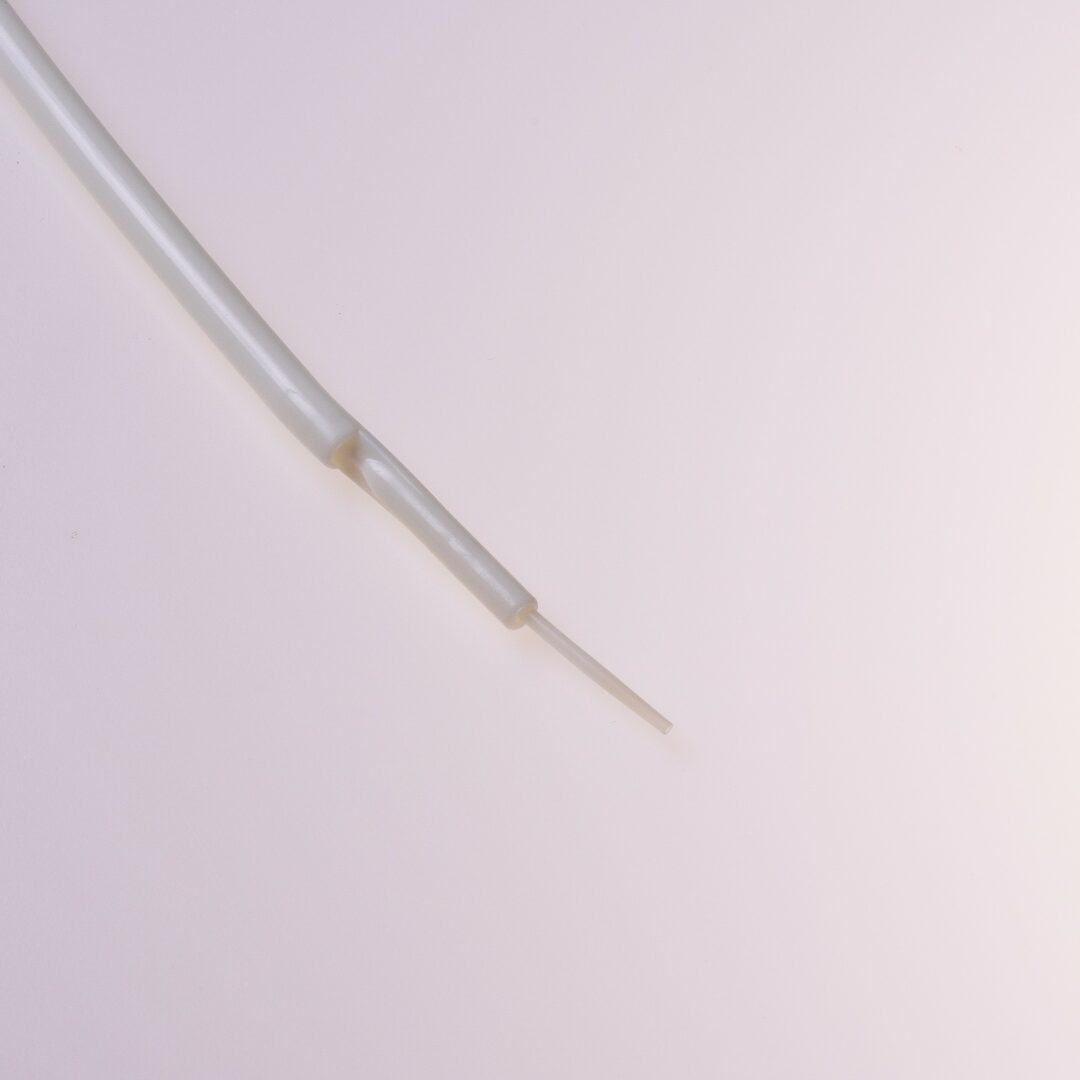

Tip Design

Der THD Titan® verfügt über ein „Tap Tip“ Spitzendesign.